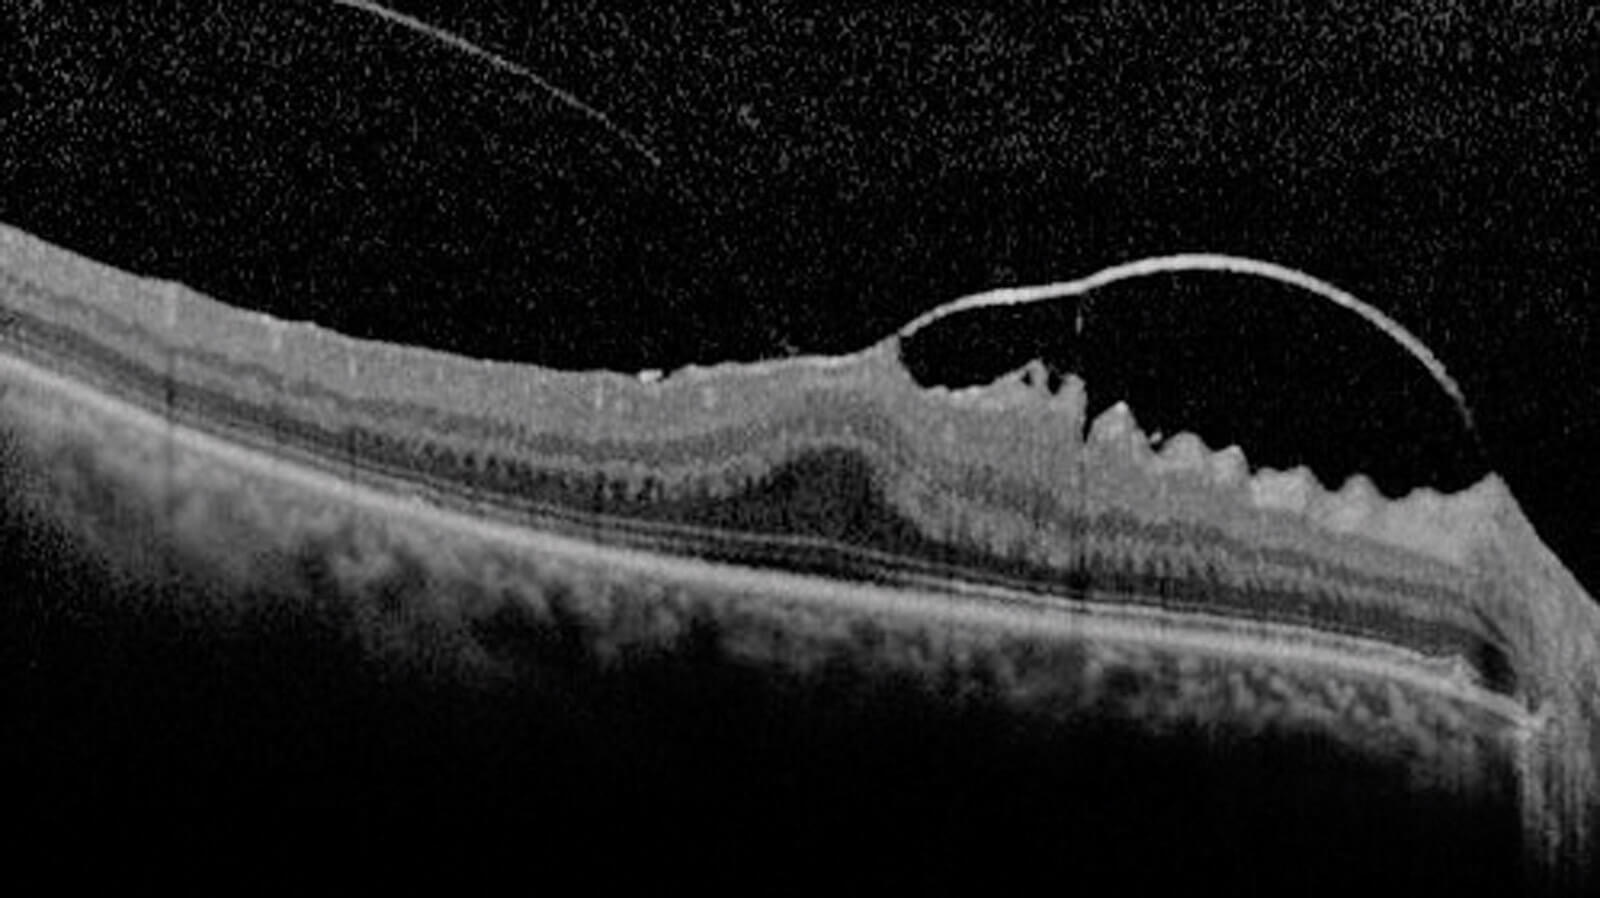

Figure 1: SD-OCT scan of focal VMA+VMT+ ERM.

Vitreo-macular adhesion (VMA): It can be described as focal or broad. It is the condition in which the vitreous adheres to the retina in a strongly anomalous way. As for the VMA, it is to be considered:

- Focal VMA with and X≤1500 microns

- Broad VMA with an X>1500 microns.

Vitreo-macular traction (VMT): This syndrome is characterised by an incomplete detachment of the vitreous (PVD). Vitreo-macular traction can be classified from the morphological point of view (as J-shaped and V-shaped) and from the point of view of the diameter (as focal or broad). From the point of view of the dimension, as for the previously mentioned VMA, we can have:

- Focal VMT with an X≤1500 microns.

- Broad VMT with an X>1500 microns.

Furthermore, VMA and VMT can present on OCT scans as either isolated (single sign) or concomitant (with other signs).

Epiretinal membrane (ERM): It is a fibro-cellular, avascular and semitranslucent membrane. This sign can be classified as:

- Idiopathic, with unidentifiable aetiology.

- Primary, caused by vitreous detachment.

- Secondary caused by another aetiology.